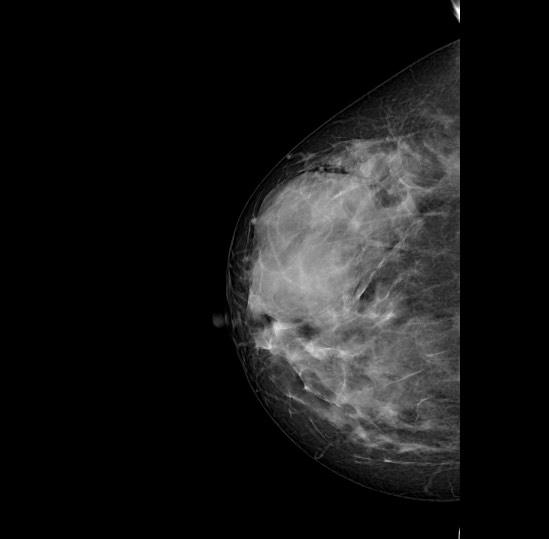

Hình ảnh chụp khối viêm trong tuyến vú. Ảnh: BVCC |

Cẩn trọng khi tiêm bất cứ chất gì vào cơ thể

Theo TS. BS Phạm Ngọc Minh, khoa Phẫu thuật Tạo hình và Vi phẫu, Bệnh viện TWQĐ 108, kết quả thăm khám lâm sàng và siêu âm cho thấy ngực bệnh nhân T.H.T có nhiều khối hỗn hợp âm bất thường trong tổ chức mô tuyến vú. Bệnh nhân được chẩn đoán viêm cấp tổ chức phần mềm vú lan tỏa.